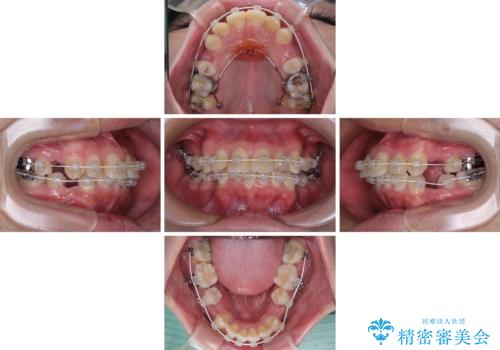

- 審美装置

- 2年8ヶ月

- 30回以上

口元はやや突出感があったため、上下左右の第一小臼歯4本を抜歯してワイヤー矯正にて抜歯矯正を行うこととしました。

また、左右ともに最後臼歯が交叉咬合になっており、外側に飛び出している上顎の最後臼歯を補助装置を利用して、積極的に内側に引き込むようにしました。